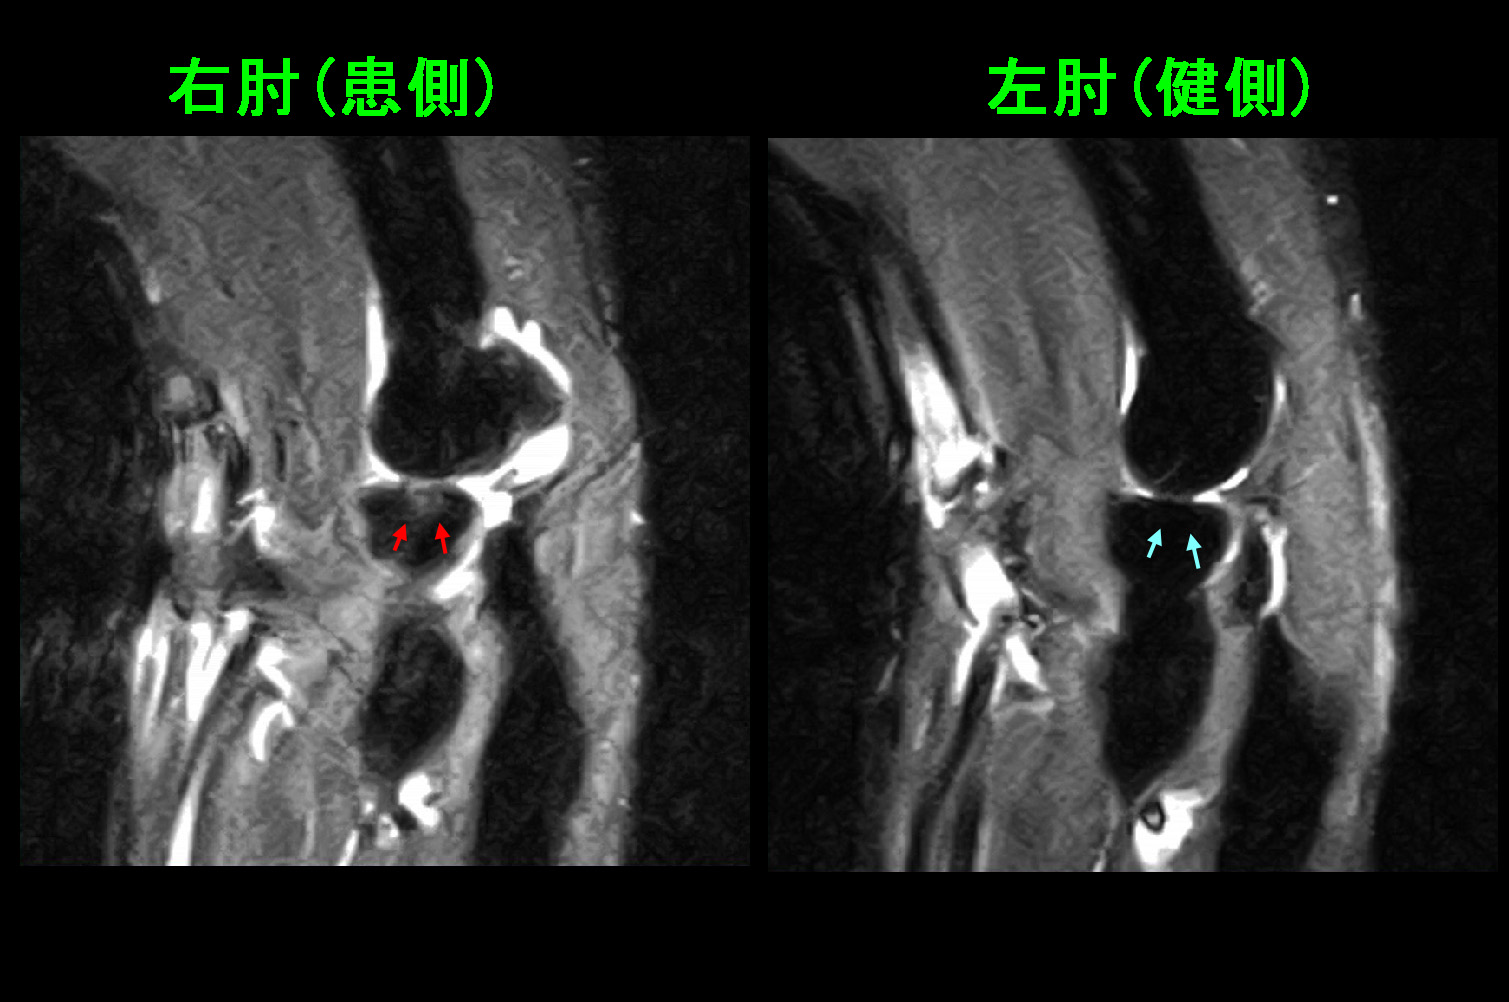

このMRI画像では赤矢印の橈骨頭部は右肘に比して骨折により広がっていて、関節面は陥凹していることが分かります。

MRIでの尺骨肘頭部は赤矢印で関節面が軽微断裂または段違いとなっていますが、このような軽微な所見は通常のレントゲン像では正常と認識されることが大半です。受傷時の肘頭骨折がこれだけの所見だったのか、もっと違う所見があったのかは分かりません。